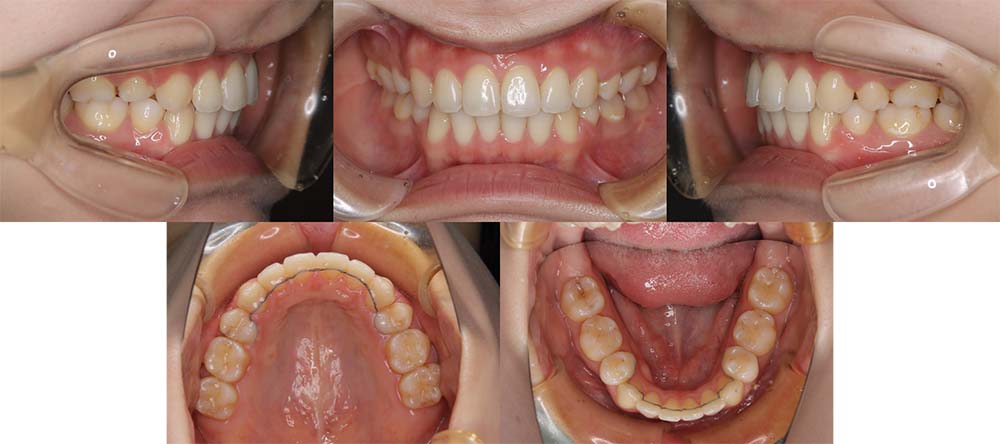

| 症例分類 | 上顎前突、叢生 |

| 診断名 | 上下叢生を伴う骨格性および歯性上顎前突 |

| 主訴 | 歯並びが悪いのが気になる、口元が気になる |

| 年齢 | 19歳5ヶ月 |

| 性別 | 女性 |

| 抜歯部位 | 上の左右第一小臼歯(2本) |

| 使用装置 | 上下裏側のワイヤー装置 |

| 治療期間 | 2年5ヶ月 |

| 保定装置 | 固定式保定装置、取り外し式保定装置(8時間) |

| 費用 |

[検査・診断料] ¥49,500 [基本施術料] ¥1,331,000 [調整料] ¥5,500/回 [抜歯] ¥5,500/本 [保定装置] ¥55,000(税込) 抜歯や虫歯治療は他院にて費用が別途かかります。(抜歯¥4,000〜10,000/本)

上顎前突で上の歯がかなり前にきているため、上顎両側第一小臼歯を抜去して治療を行いました。上の前歯をしっかりと舌側に移動しないといけないため、矯正用アンカースクリューを使用しました。また、下顎はわずかに歯の間の削合(ディスキング)を行い、初診時より歯が前方に出ないように治療を進めました。

口唇閉鎖不全もありましたが、上の前歯が舌側に移動することにより改善することができ、問題なく咬合させることができました。